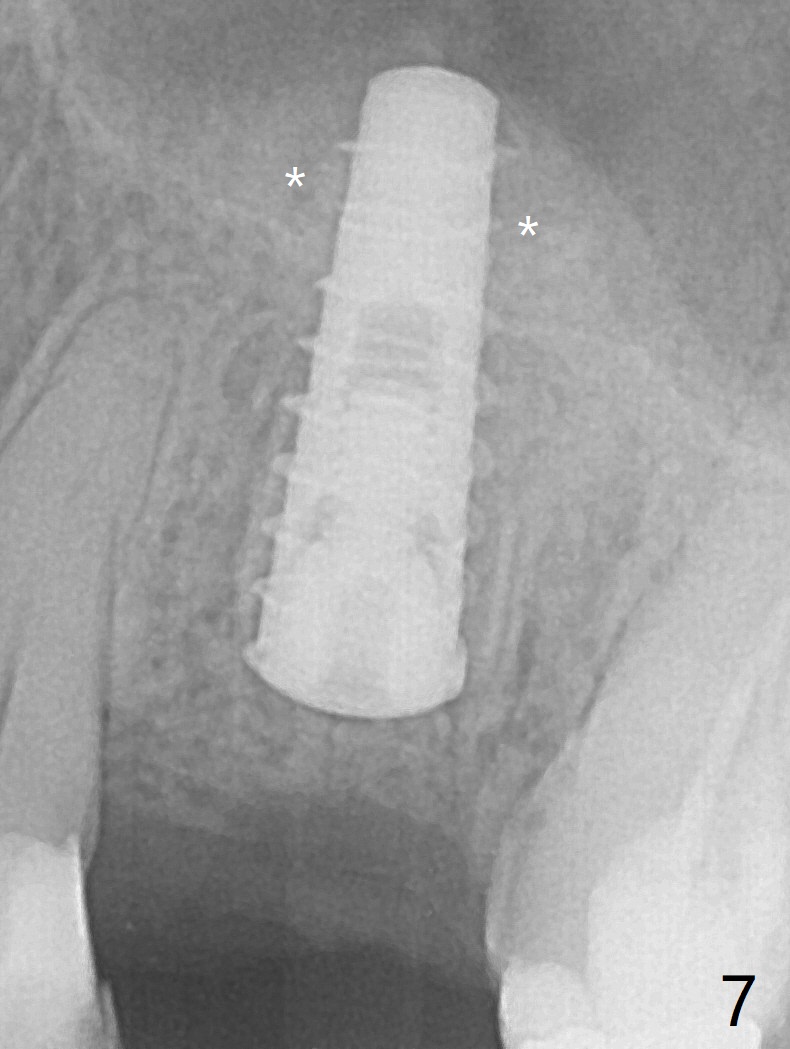

The patient with the anterior cross bite at the left lateral and canine and incipient Class V caries returns to clinic for #13 residual root extraction (Fig.1,2). There is no quality root structure (Fig.2) or space (Fig.3) for socket sheath. Two amalgam carriers of Vanilla is inserted and pushed by the 4x11 mm dummy implant for sinus lift (Fig.4 *). When the same sized final implant (4x11 mm) is placed, a 5.5 mm bone profile drill is used to trim the proximal crests (Fig.5 * sticky bone packed in the buccal and palatal gaps). In fact the implant turns when a 4.5x4(3) mm pair abutment is tightened. The implant is backed up; with a healing screw, sticky bone is placed (Fig.6 *) and then covered with a piece of PRF and a part of GEM cap. The wound is sutured with 4-0 PGA; periodontal dressing is applied. The implant is somewhat over-seated without the bone graft covering the apical end of the implant (Fig.7, as compared to Fig.4). A 4.5 mm implant should be placed. The GEM Cap appears to be absent 9 days postop, while the periodontal dressing dislodged in 1 week (Fig.8). It appears that the existing abutment at #15 is incompletely seated (Fig.3, 5.5x4(2) mm). After use of 5.5 and 6.0 mm bone profile drills, a 5x4(3) mm abutment is placed with 35 Ncm torque. In fact the bone graft coronal to the implant remains (Fig.9 *) in spite of apparent loss of the overlying PRF and GEM cap (Fig.8). After use of a 4.6 mm profile drill, a 5.5x3 mm healing abutment is placed 4.5 months postop (Fig.10). Without a provisional at #13 for ~ 4 months, there is a gap between crowns at #14 and 15 (not shown due to angulation). Impression is taken for #13 crown fabrication 5.5 months postop and for #15 crown repair (addition of porcelain for the mesial contact, Fig.11). It appears critical for a provisional to maintain the position of the neighboring tooth.